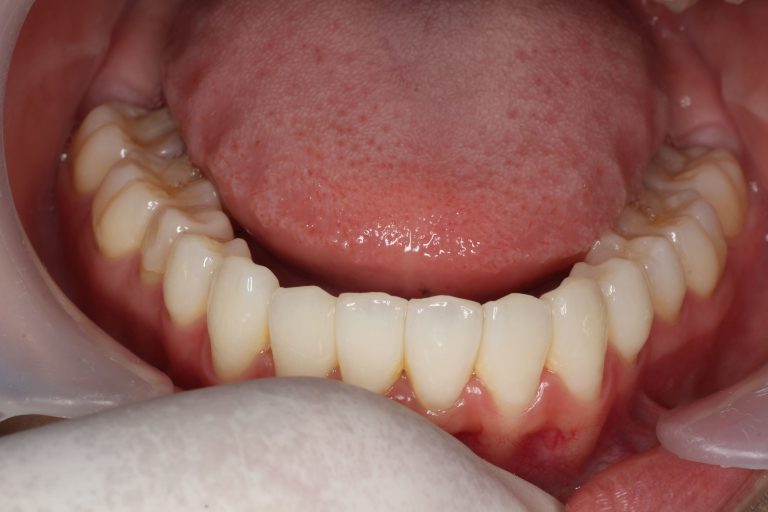

Before

After

| 主訴 | 歯並びの乱れ(叢生)があり、口元の突出感を抑えたい |

| 治療内容 | インビザラインを用いた治療 (非抜歯ケース) |

| 治療期間 | 1年7ヶ月 |

| 治療費用 | 基本料金:660,000円 調整料:3,300円 × 24回 |

| リスク | 取り外し式装置で、1日24時間中22時間使用しなければならず、しっかりと装置を装着できないと歯は思ったように動きません。 |